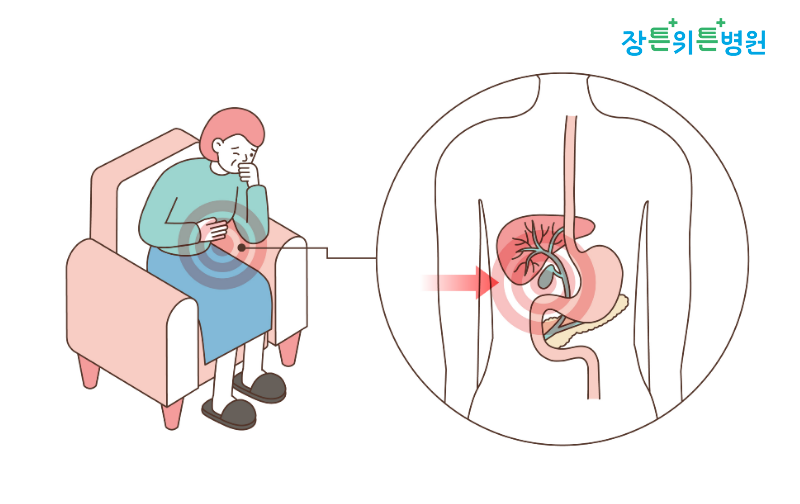

2. 담석증상 담석증의 증상 음담석의 위치에 따라 여러 가지가 나타납니다.담낭 담석의 경우는 대개 증상이 없는 경우가 많으며, 건강 진단 시에 우연히 발견됩니다.이 경우 약 80%는 평생 특별한 증상이나 합병증 없이 지내는 경우가 많으므로 담낭에 염증이 없으면 그대로 관찰해도 무방합니다.

하지만 어떤 경우는 가스 부족이나 복통, 공복감이나 트림 등의 증상이 나타날 수 있습니다.작은 담석이 담낭관을 통해 담낭에서 빠져 나와 담관의 일부를 막으면 담낭애의 압력이 높아져 갑자기 심한 복통이 발생합니다.이때 통증은 명치 아래, 오른쪽 상복부에 통증이 있으며, 양쪽 견갑골 사이로 오른쪽 견갑골 부분이 아프고 주로 식후에 악화되는 양상을 보입니다.또한 담석에 의한 통증은 기름진 음식에 의해 유발될 수 있는데 자세 변화에 관계없이 30분에서 수시간에 걸쳐 발생합니다.